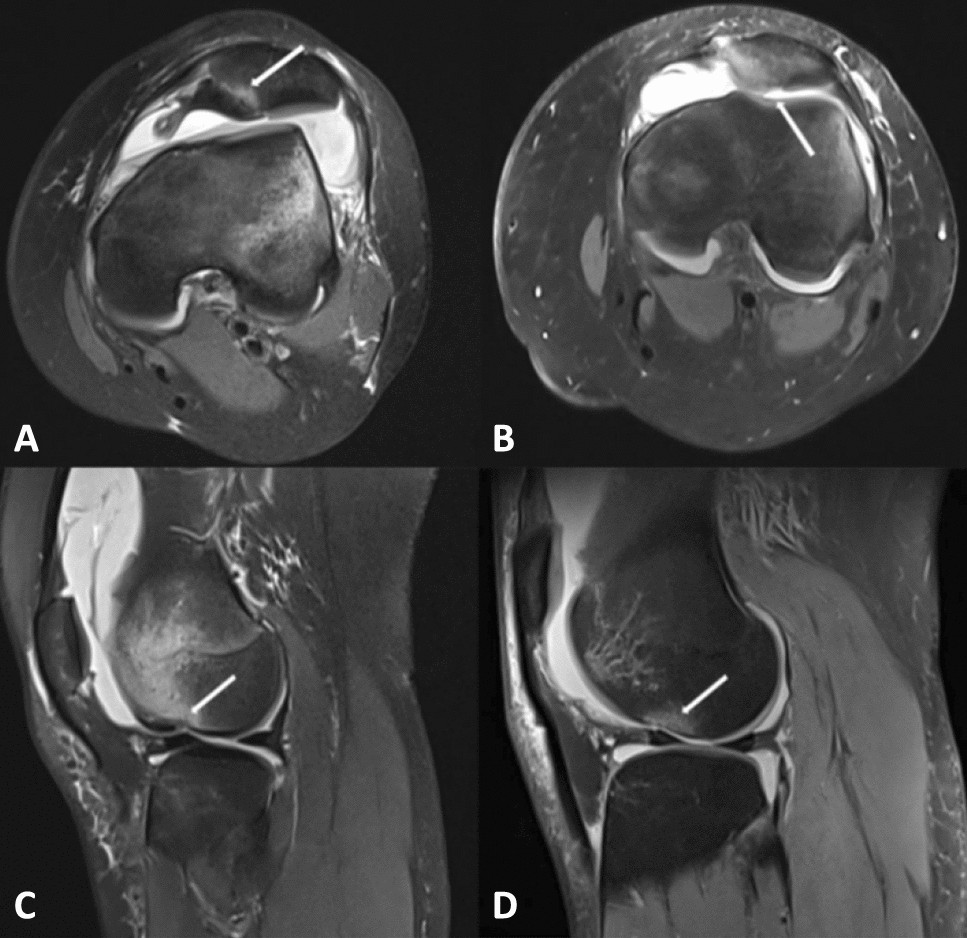

Figure 1

(A,B) Depict the axial MRI scans illustrating osteochondral damage to the medial patella (white arrow). (C,D) Illustrating osteochondral damage to the lateral femoral condyle (white arrow).